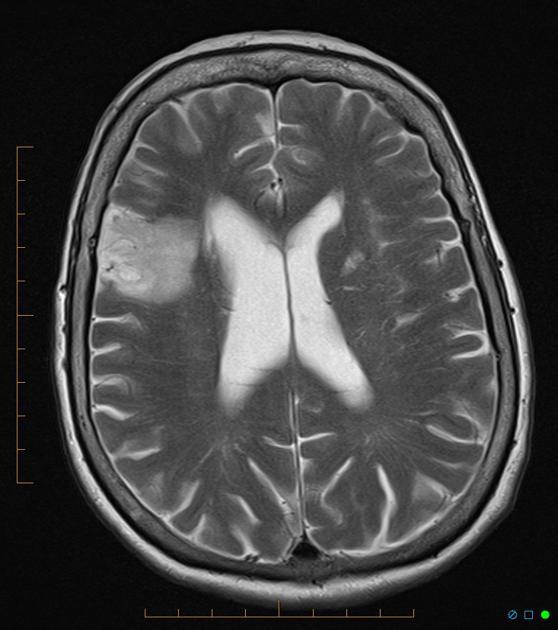

Cortical pseudolaminar necrosis

Cortical pseudolaminar necrosis, also known as cortical laminar necrosis and simply laminar necrosis, is the (uncontrolled) death of cells in the (cerebral) cortex of the brain in a band-like pattern with a relative preservation of cells immediately adjacent to the meninges.

It is seen in the context of cerebral hypoxic-ischemic insults, i.e. strokes.

Hyperintense on both T1 and T2!!!